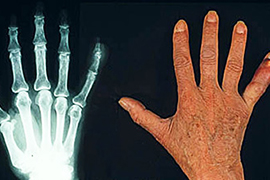

Диагноз подагры можно поставить клинически без проведения артроцентеза

Существует схема диагностики подагры, предсказательная ценность которой подтверждена для общей популяции больных, для больных, обращающихся первично, к врачу общей практики или к терапевту.

Эта схема не предполагает проведения инвазивной процедуры артроцентеза. «Золотым стандартом» диагностики подагры является анализ синовиальной жидкости и обнаружение кристаллов моноурата натрия. Нередко при недоступности оборудования для врачей-специалистов (во вторичном звене системы здравоохранения) используется та же самая схема, что в первичном звене. Нидерландские исследователи валидировали этот диагностический инструмент для популяции больных, уже наблюдающихся врачом-специалистом.

В исследование были включены 390 больных с моноартритом. Была проведена оценка по диагностической шкале, которая включает следующие пункты: мужской пол, атаки артрита в анамнезе, развитие симптомов в течение суток или быстрее, покраснение сустава, вовлечение первого плюснефалангового сустава, наличие гипертензии или других заболеваний сердечно-сосудистой системы, уровень мочевой кислоты в крови более 5,88 мг/дл. Всем больным был выполнен артроцентез с анализом синовиальной жидкости. Пациенты наблюдались продолжительное время (до 17 месяцев) для выяснения причин артрита в случае неопределенности.

Кристалы моноурата натрия были обнаружены у 219 больных (56%). Прогностическая ценность положительного результата, если определить положительный результат как 8 и более баллов, составила 0,87. Прогностическая ценность отрицательного результата, если определить его как 4 балла и менее, составила 0,95. Все оцененные параметры информативности диагностической схемы указывали на ее высокую точность и надежность в изученной популяции больных.

Авторы считают, что использование этой клинической шкалы позволит сократить количество инвазивных процедур и точнее выделить тех, больных, которым необходим артроцентез и наблюдение ревматолога.